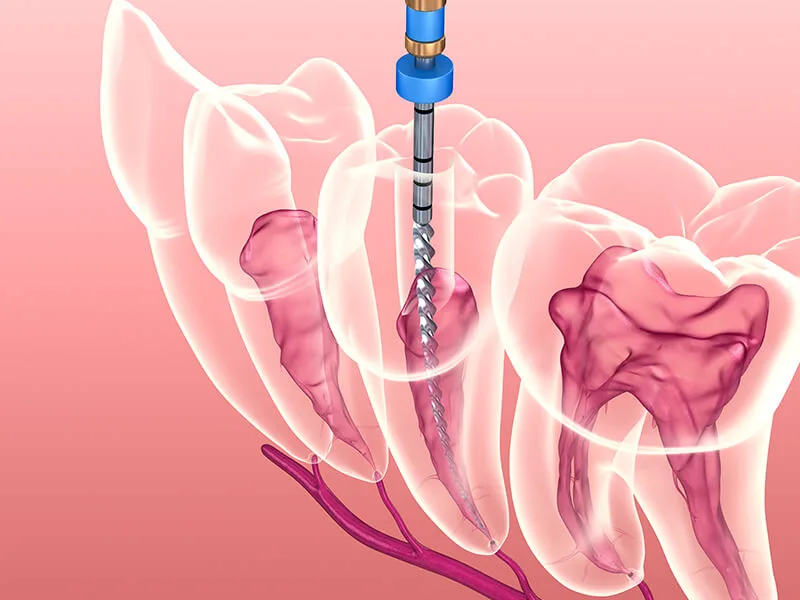

Etapas do Procedimento

O tratamento geralmente começa com uma avaliação clínica e radiográfica.

Em seguida, o dentista realiza a anestesia local e a remoção da polpa danificada.

Após a limpeza, os canais são desinfetados e selados.